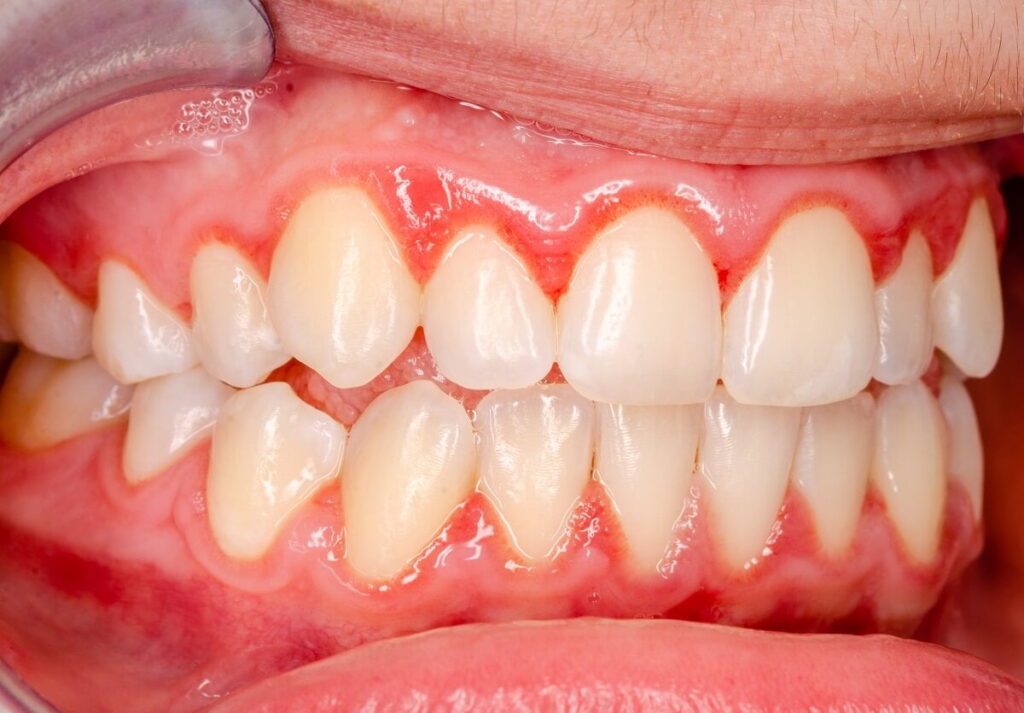

Gingivitis is the first stage of gum sickness. It happens when your gums get red, swollen, or bleed. The main cause is plaque, sticky germs that grow on your teeth every day. If plaque is not cleaned away by brushing or flossing, it irritates your gums.

Gingivitis is mild and can go away if you take care of your teeth.

Signs of Gingivitis :

- Red or puffy gums

- Gums that bleed when brushing or flossing

- Bad breath

- Sore gums

- Gums pulling slightly away from teeth